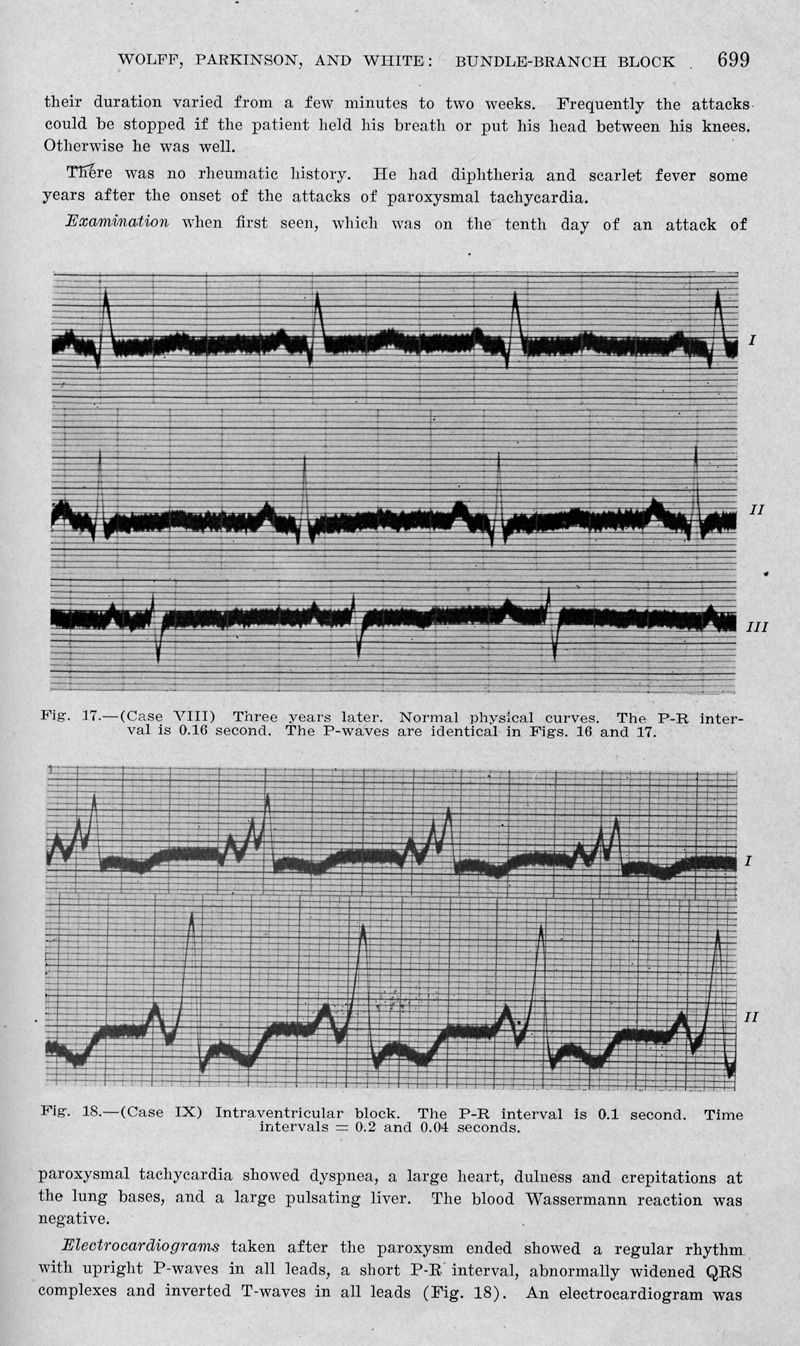

WOLFF, Louis / PARKINSON, J. / WHITE, P.

Bundlebranch block with short P-R interval in healthy young people prone to paroxysmal tachycardia

In : [The] American heart journal, 1930, Vol. 5, pp. 685-704